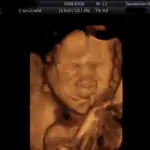

3D/4D ultrazvuk

Tyto fotografie jsou pořízené přístrojem Voluson 730